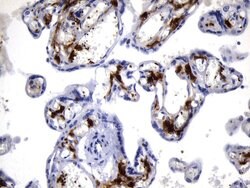

F13A1 Mouse anti-Human, Clone: UMAB243, liquid, UltraMAB™

This gene encodes the coagulation factor XIII A subunit. Coagulation factor XIII is the last zymogen to become activated in the blood coagulation cascade. Plasma factor XIII is a heterotetramer composed of 2 A subunits and 2 B subunits. The A subunits have catalytic function, and the B subunits do not have enzymatic activity and may serve as plasma carrier molecules. Platelet factor XIII is comprised only of 2 A subunits, which are identical to those of plasma origin. Upon cleavage of the activation peptide by thrombin and in the presence of calcium ion, the plasma factor XIII dissociates its B subunits and yields the same active enzyme, factor XIIIa, as platelet factor XIII. This enzyme acts as a transglutaminase to catalyze the formation of gamma-glutamyl-epsilon-lysine crosslinking between fibrin molecules, thus stabilizing the fibrin clot. It also crosslinks alpha-2-plasmin inhibitor, or fibronectin, to the alpha chains of fibrin. Factor XIII deficiency is classified into two categories: type I deficiency, characterized by the lack of both the A and B subunits; and type II deficiency, characterized by the lack of the A subunit alone. These defects can result in a lifelong bleeding tendency, defective wound healing, and habitual abortion.Specifications

| Immunohistochemistry (Paraffin) | |